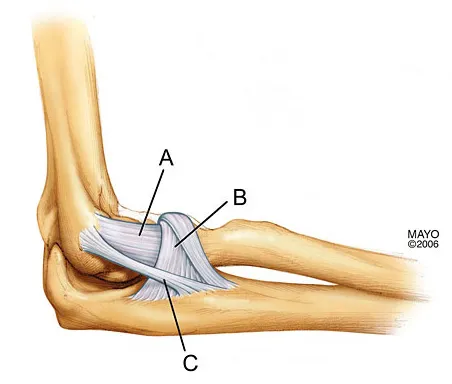

Question 28

What is the structure indicated by the letter "A" in Figure 21?

Explanation